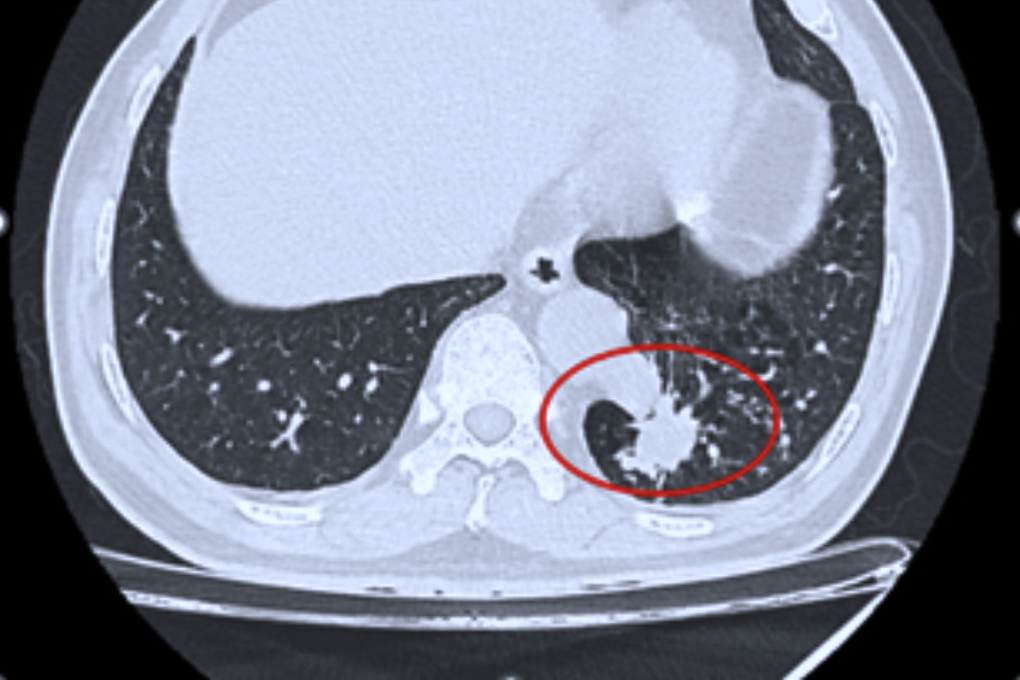

Ông N.N.T. (56 tuổi, ngụ tỉnh Tây Ninh) tình cờ phát hiện tổn thương thùy dưới phổi trái khi đi khám tổng quát. Tại Bệnh viện Bình Dân (TPHCM), các bác sĩ chẩn đoán ông có khối phổi biệt lập nội thùy, kích thước 23×26 mm.

Đáng chú ý, động mạch nuôi khối này xuất phát trực tiếp từ động mạch chủ xuống với đường kính lên tới 17mm – là kích thước rất lớn và đầy rủi ro nếu người bệnh không được điều trị.

Kết quả chụp CT vùng ngực của bệnh nhân (Ảnh: BV).